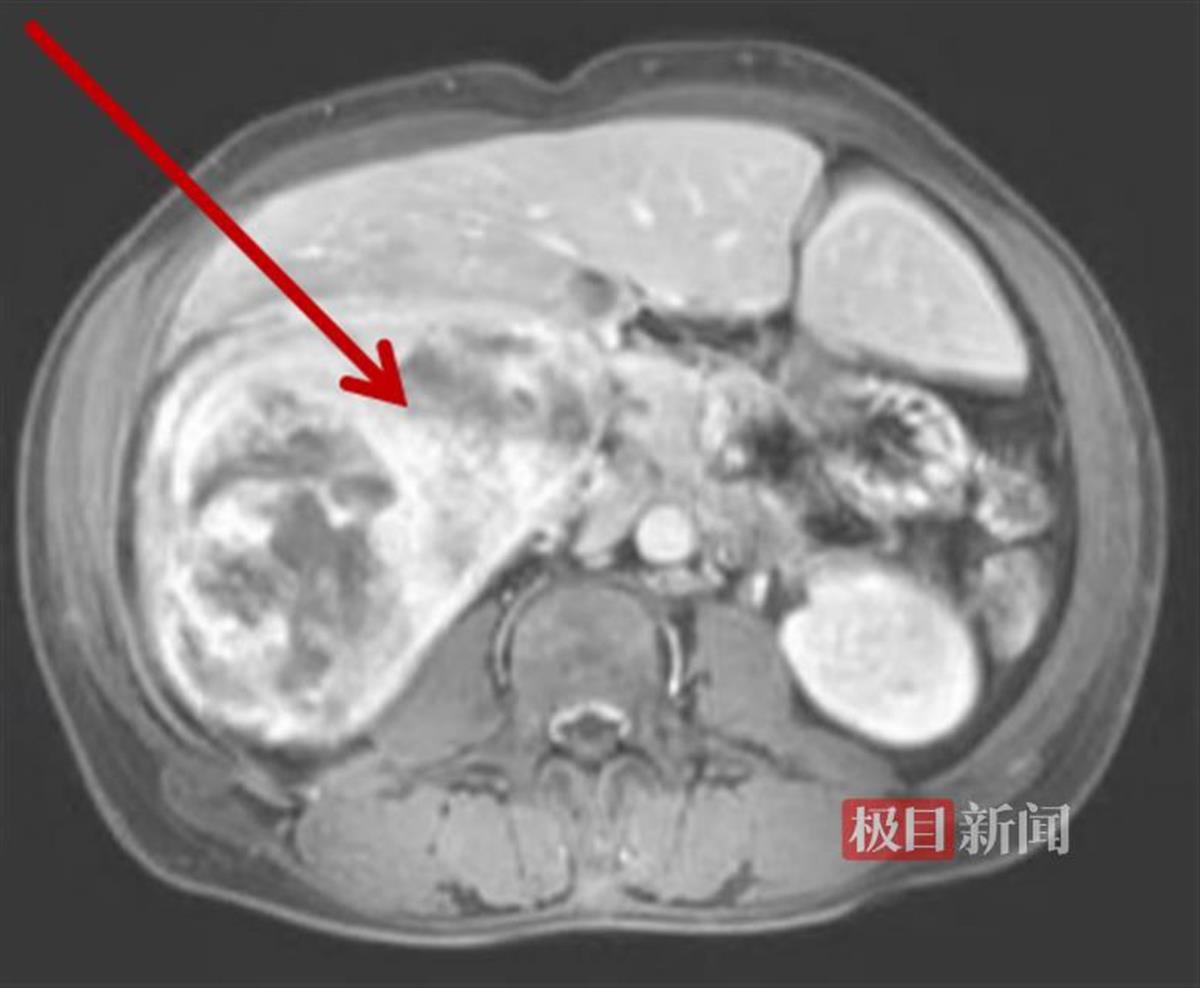

经CT检查发现,他的肝脏上长了个巨大的球形肿瘤,直径约20厘米。更凶险的是,它随时有破裂大出血的风险,必须尽快手术。考虑到疾病凶险,当地医院紧急联系后将患者转至武汉协和医院车谷院区肝胆胰外科/肝脏移植中心,并在短时间内完成术前检查。

术前影像检查发现肝脏巨大肿瘤

经过三维重建评估,患者的肝脏重约4795克,是正常肝脏的3倍多,其中肝脏肿瘤的重量约2888克,占了肝脏重量的一半以上。经过评估,患者肝脏上的病灶是单个的,且肿瘤呈膨胀性生长,从影像学上看有完整的包膜,属于早期肝癌,切除后效果会比较好。